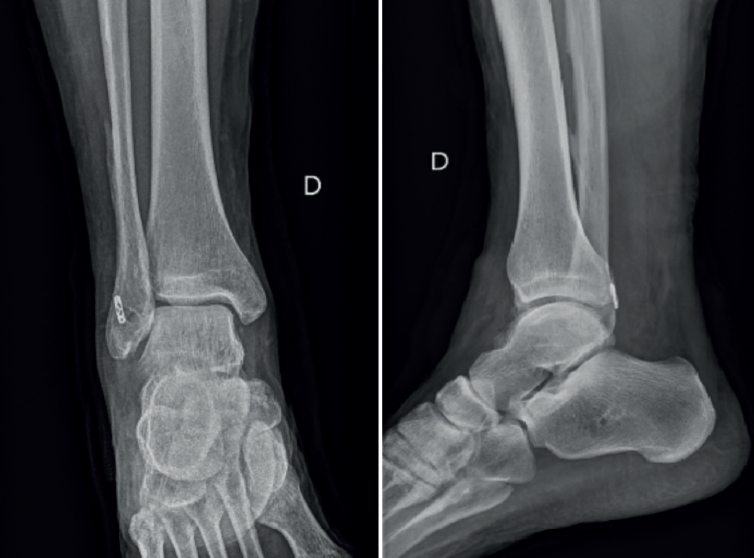

El paciente presentó un postoperatorio correcto en el cual se realizó un protocolo de inmovilización postoperatoria con movilización temprana y fisioterapia enfocada en mejorar la movilidad y fortalecer la musculatura del tobillo, con mejora en cuanto al dolor y la inestabilidad subjetiva. Un año después, el paciente volvió a consultar por dolor localizado en la cara posterolateral del tobillo. A la exploración, presentaba hinchazón lateral e hiperalgesia sobre el maléolo lateral. El rango de movimiento estaba preservado. Además, se evidenció dolor durante los movimientos de eversión. El paciente describió una sensación de chasquido en la cara lateral del tobillo. La prueba de cajón anterior no era negativa, por lo que cabía considerar la posibilidad de un fracaso de la reparación o aflojamiento de las plastias ligamentosas. Las radiografías simples demostraron que no había desplazamiento del dispositivo de fijación de la fíbula, como se muestra en la Figura 1.

Figura 1. Control radiográfico postoperatorio donde se ve el anclaje TightRope® en la parte posterior del peroné.